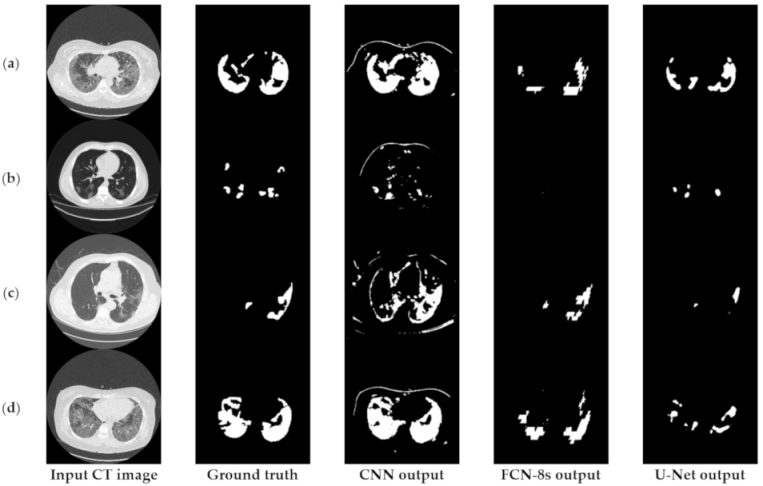

6.3.1. Comparisons with Other Deep Learning Models